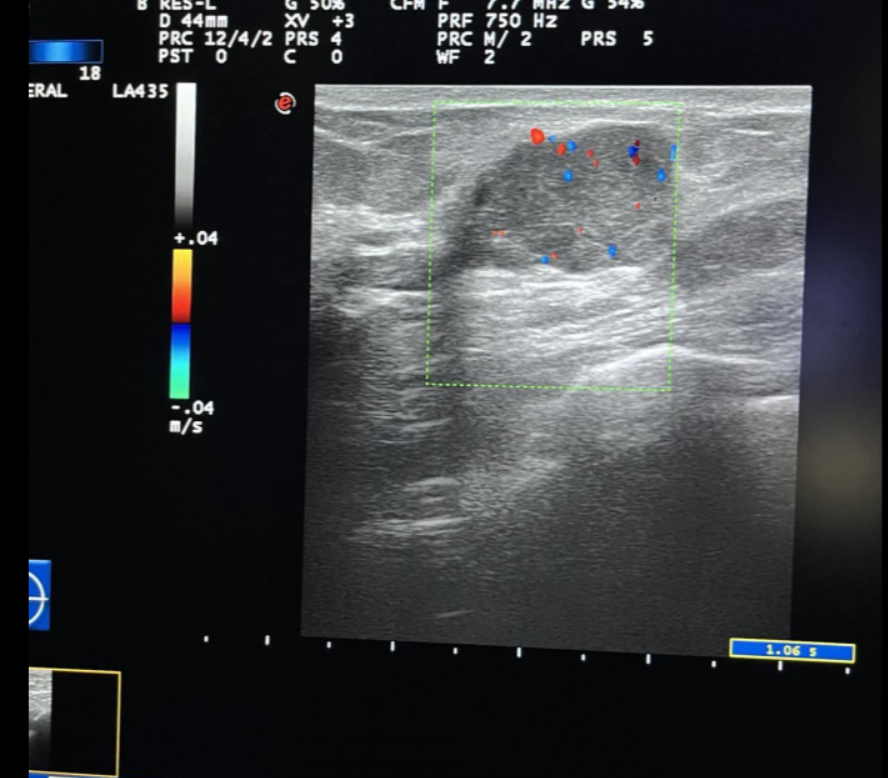

Strain elastography – historically is the earliest elastography technique, where external tissue compression is applied and comparison between ultrasound images and images after compression. The least deformed are the most rigid areas of the image, and the most deformed areas are the softest (7) (Figure1).

Elastography is based on the fact that in malignant tumors the density of cells increases, which changes the elasticity of the tissue itself. Elastography provides an assessment of the deformation of all tissues (fatty, fibroadenomas, or solid lesions) and shows in real-time that benign nodes such as fibroadenomas, papillomas, etc. (Figure1). In malignant lesions, there is a certain inelasticity of the tissue, which is usually the result of neoplastic infiltration of the interstitium, the desmoplastic reaction intra- and extra-nodular. Such is the case with ductal carcinomas, squamous type of carcinoma. Exceptions are some tumors of the mucinous or papillary carcinoma type which are of low malignant consistency.

Figure1. Elastography shows in real-time benign nodes such as fibroadenomas and papillomas.

Figure 4. Inv. Intraductal Breast Carcinoma (same patient) – Sonoelastography, US